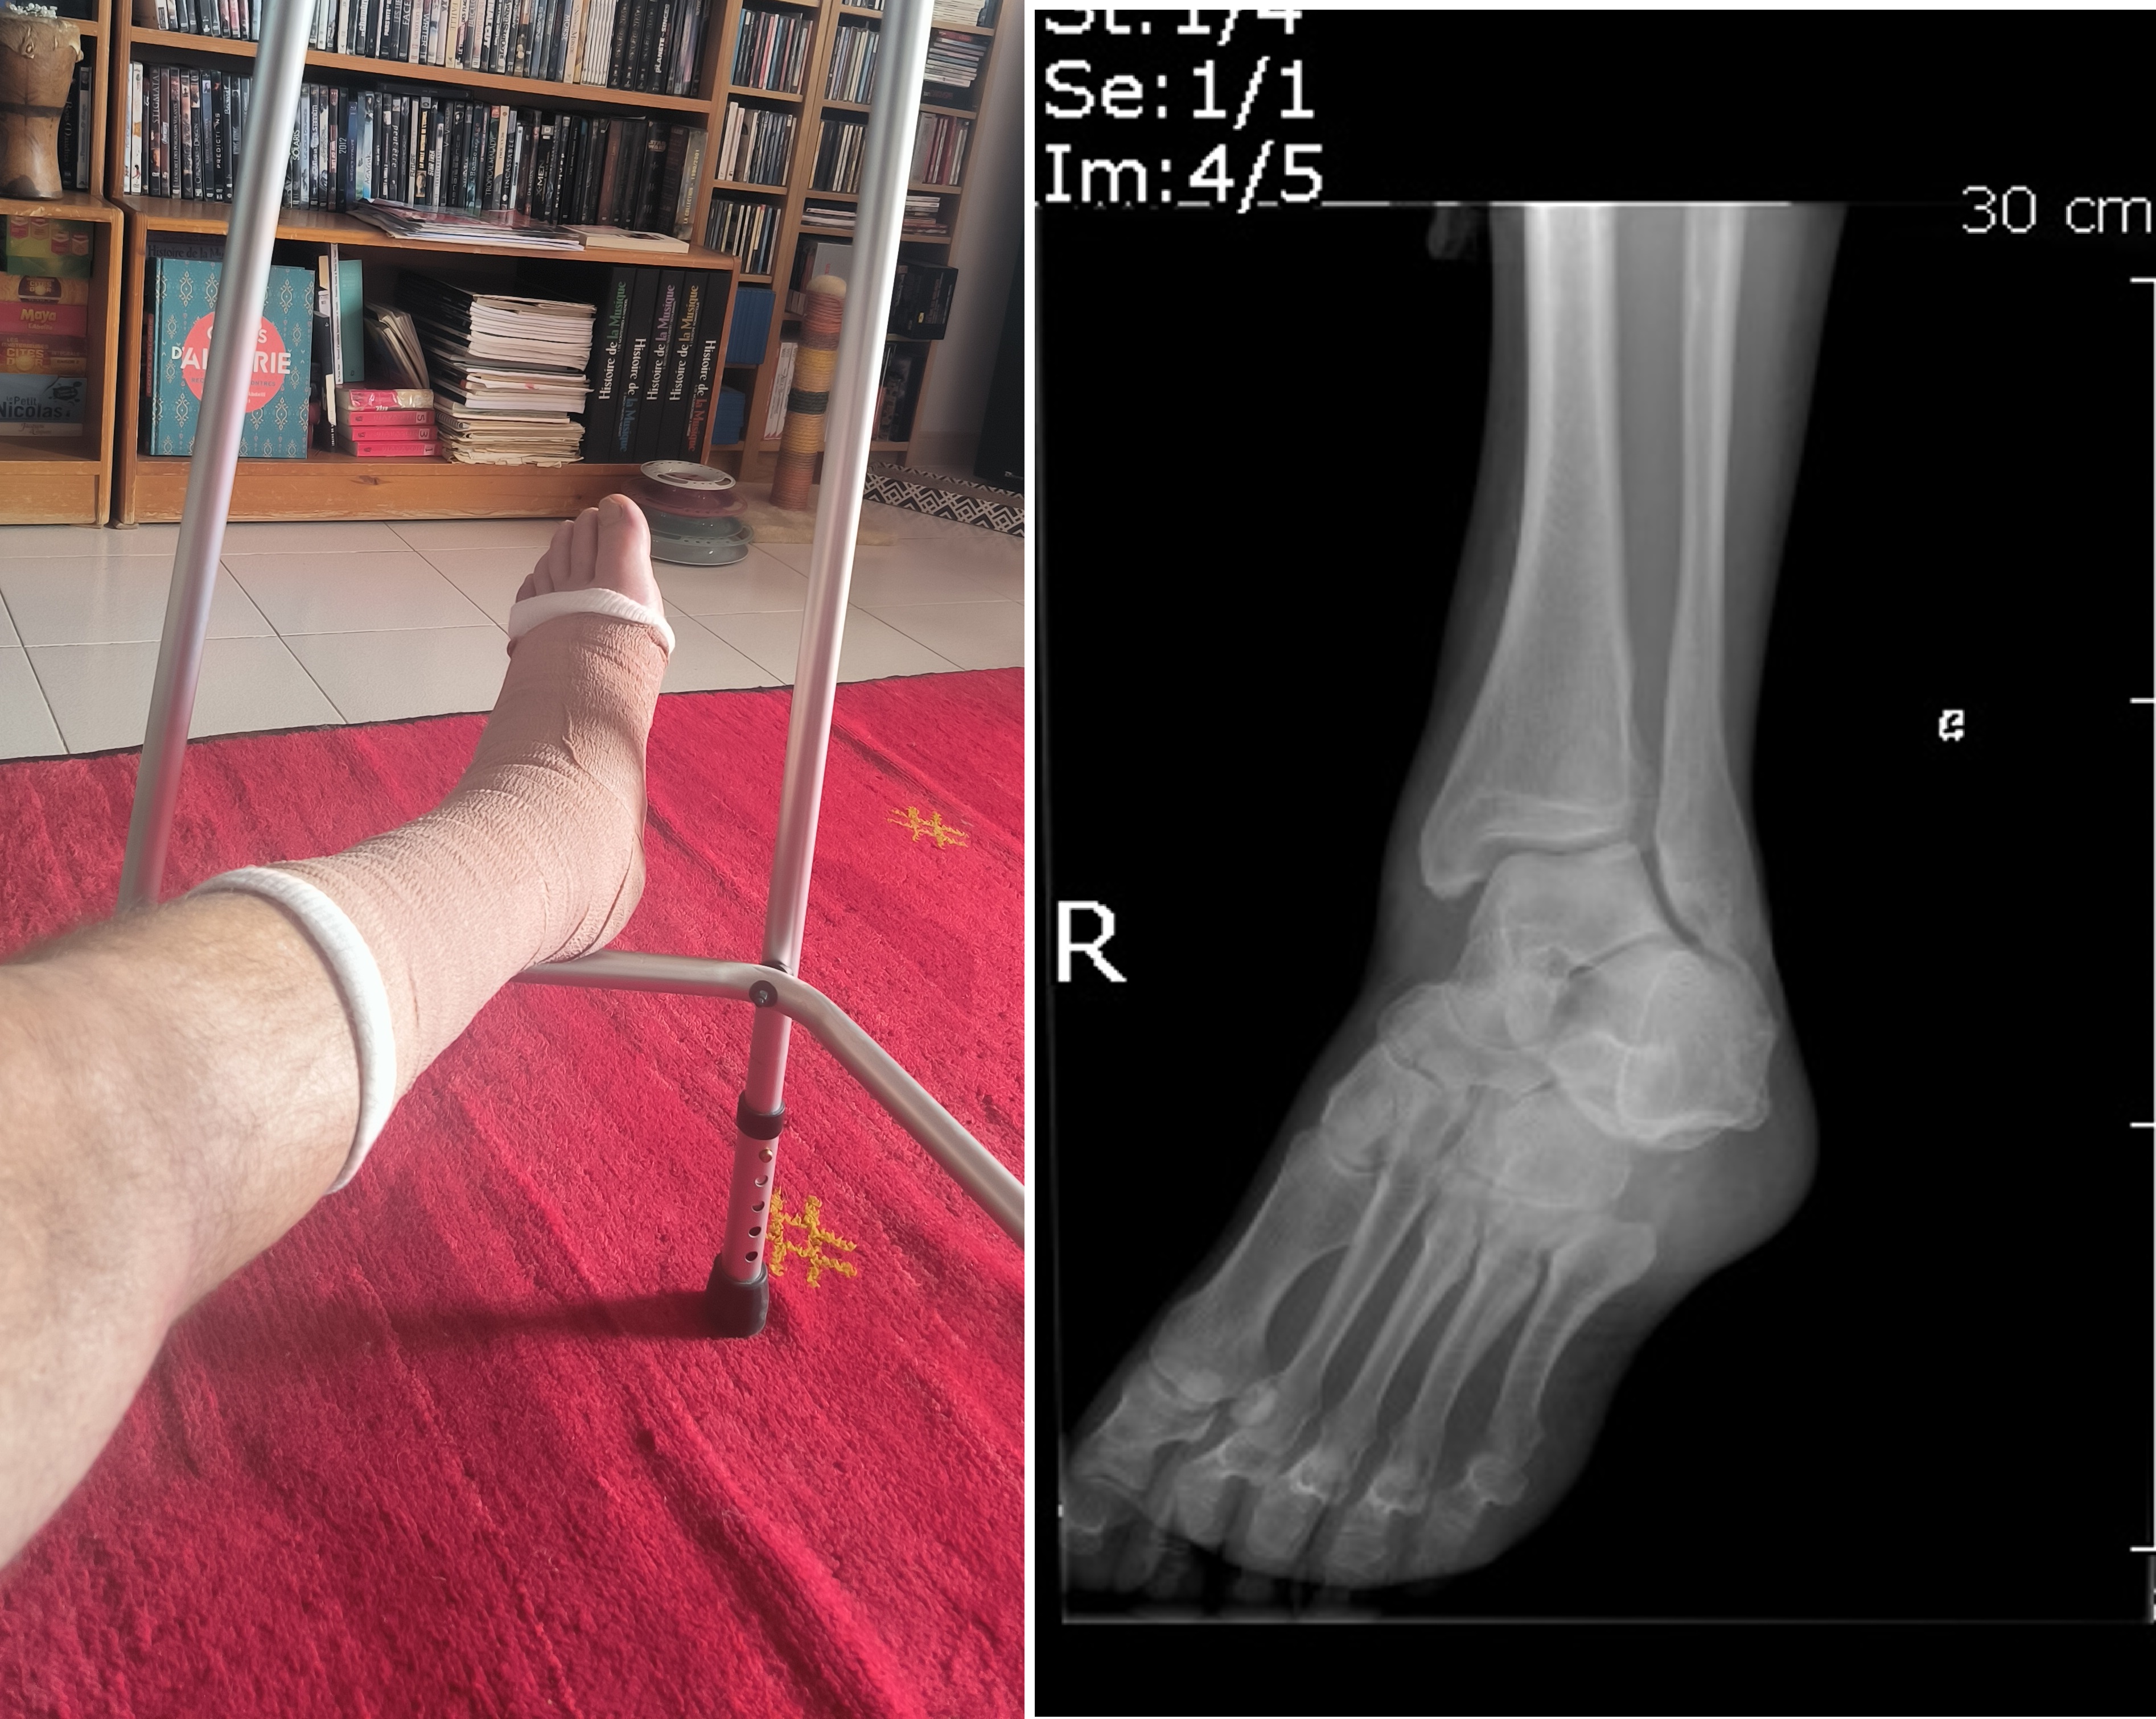

Radio, médecin, le diagnostic est rapide, fracture de la malléole du tibia et déboîtement… il faut plâtrer et il y aura de la kiné… Le programme se met en place, arthroscanner et suivi prévu, et donc béquilles fournies par l’hôpital, et fauteuil prêté par un voisin (merci arnaud !)